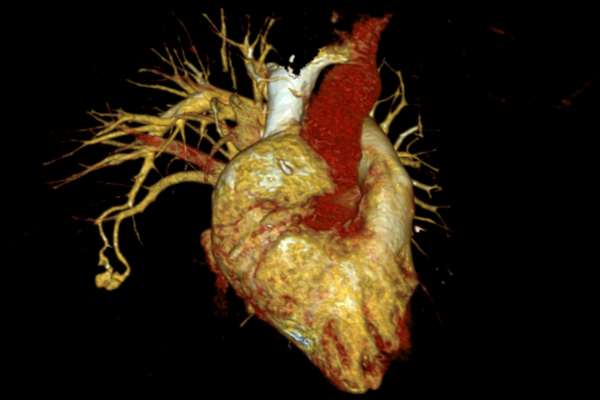

Pulmonary embolism occurs when large blood clots block lung arteries, causing sudden breathlessness, chest pain, and collapse.

Thrombectomy removes the clot directly, restores blood flow, reduces strain on the heart, and saves life in high-risk patients.